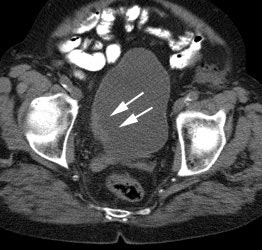

|

Genitourinary activity: The image below demonstrates activity within the collecting system of a transplanted kidney (black arrows). This should not be mistaken for an abnormality. |

|

|

|

Bladder cancer: Dilute urinary activity in this patient's bladder allowed accurate detection of their bladder cancer (white arrows on CT, black arrows on PET scan). In general, urinary excretion of FDG limits evaluation of urinary tract malignancies, however, hydration and diuresis can improve diagnostic accuracy. |

|

|